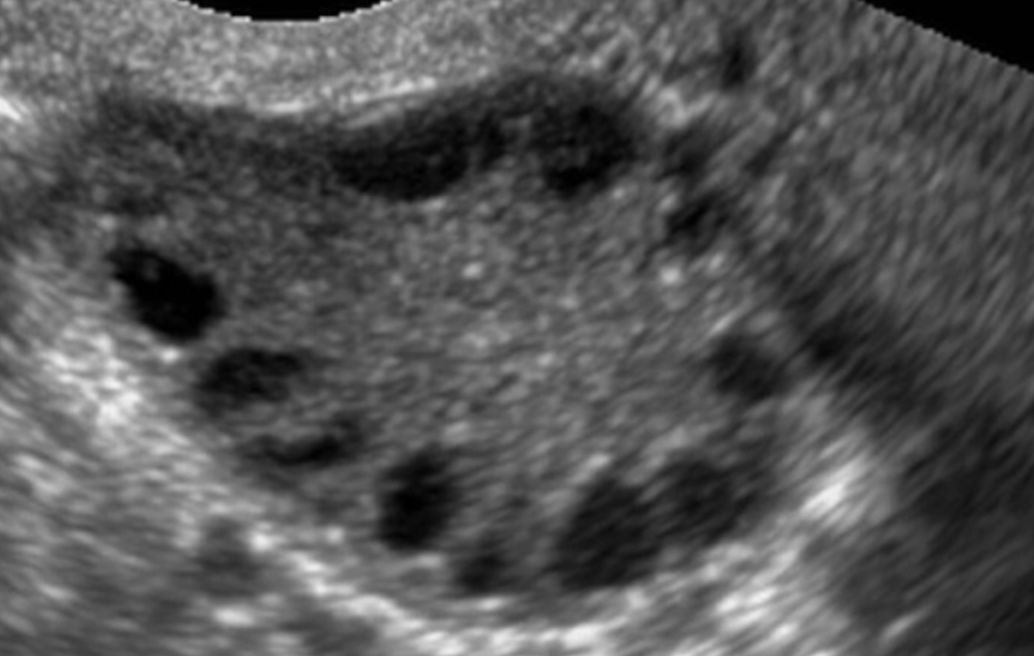

3. polycystic ovaries on ultrasound

1. 12 or more in 1 or both ovaries (string of pearls)

2. ovarian volume over >10cm3

pelvic ultrasound scan

transvaginal ultrasound is gold standard for visualising the ovaries - string of pearls as follicles arranged around the periphery of the ovary or ovarian volume of 10cm3 or more

not reliable in adolescents at diagnosing PCOS